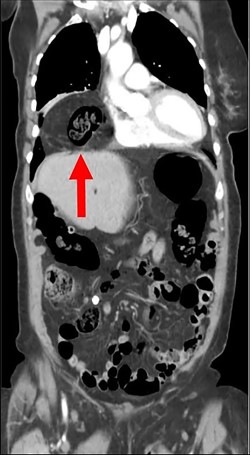

During the hospitalization, initial cardiac workup with 12-lead electrocardiogram and serial troponins was negative. The patient’s oncologic medications were held without improvement of the pain as well as to prevent leukopenia and neutropenia, if surgery was indicated. Palliative care was unable to achieve adequate pain control with oral and IV medications, and the patient did not want to pursue hospice care. Surgical consultation was obtained, and further evaluation with a CT scan of the chest, abdomen and pelvis with oral and IV contrast demonstrated an anteromedial diaphragmatic defect through which a prominent amount of mesenteric fat and a portion of the colon herniated representing a Morgagni hernia (Figs. 1–4). An increase in the size of the previously known PEH as well as the Morgagni hernia was noted. Due to continued chest pain unrelieved by opioids, a joint decision was made between surgeon, oncologist and the patient to proceed with surgery. She underwent successful robotic laparoscopic repair of the Morgagni hernia and PEH with dulex mesh for reinforcement. Her chest pain subsequently resolved. The patient gradually tolerated oral feeds and was eventually discharged in stable condition.

The CT abdomen and pelvis with oral contrast from 2015 pictured above led to an initial diagnosis of a Morgagni hernia, identified by the red arrow.